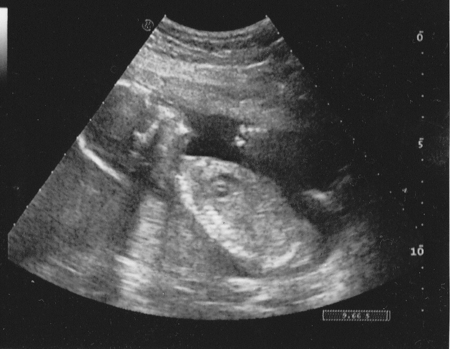

Так что выкладываю единственное фото УЗИ, которое удалось выклянчить у узиста в роддоме.

тут нам 19 недель.

зы: четко видно 5 пальчиков левой ручки!!!